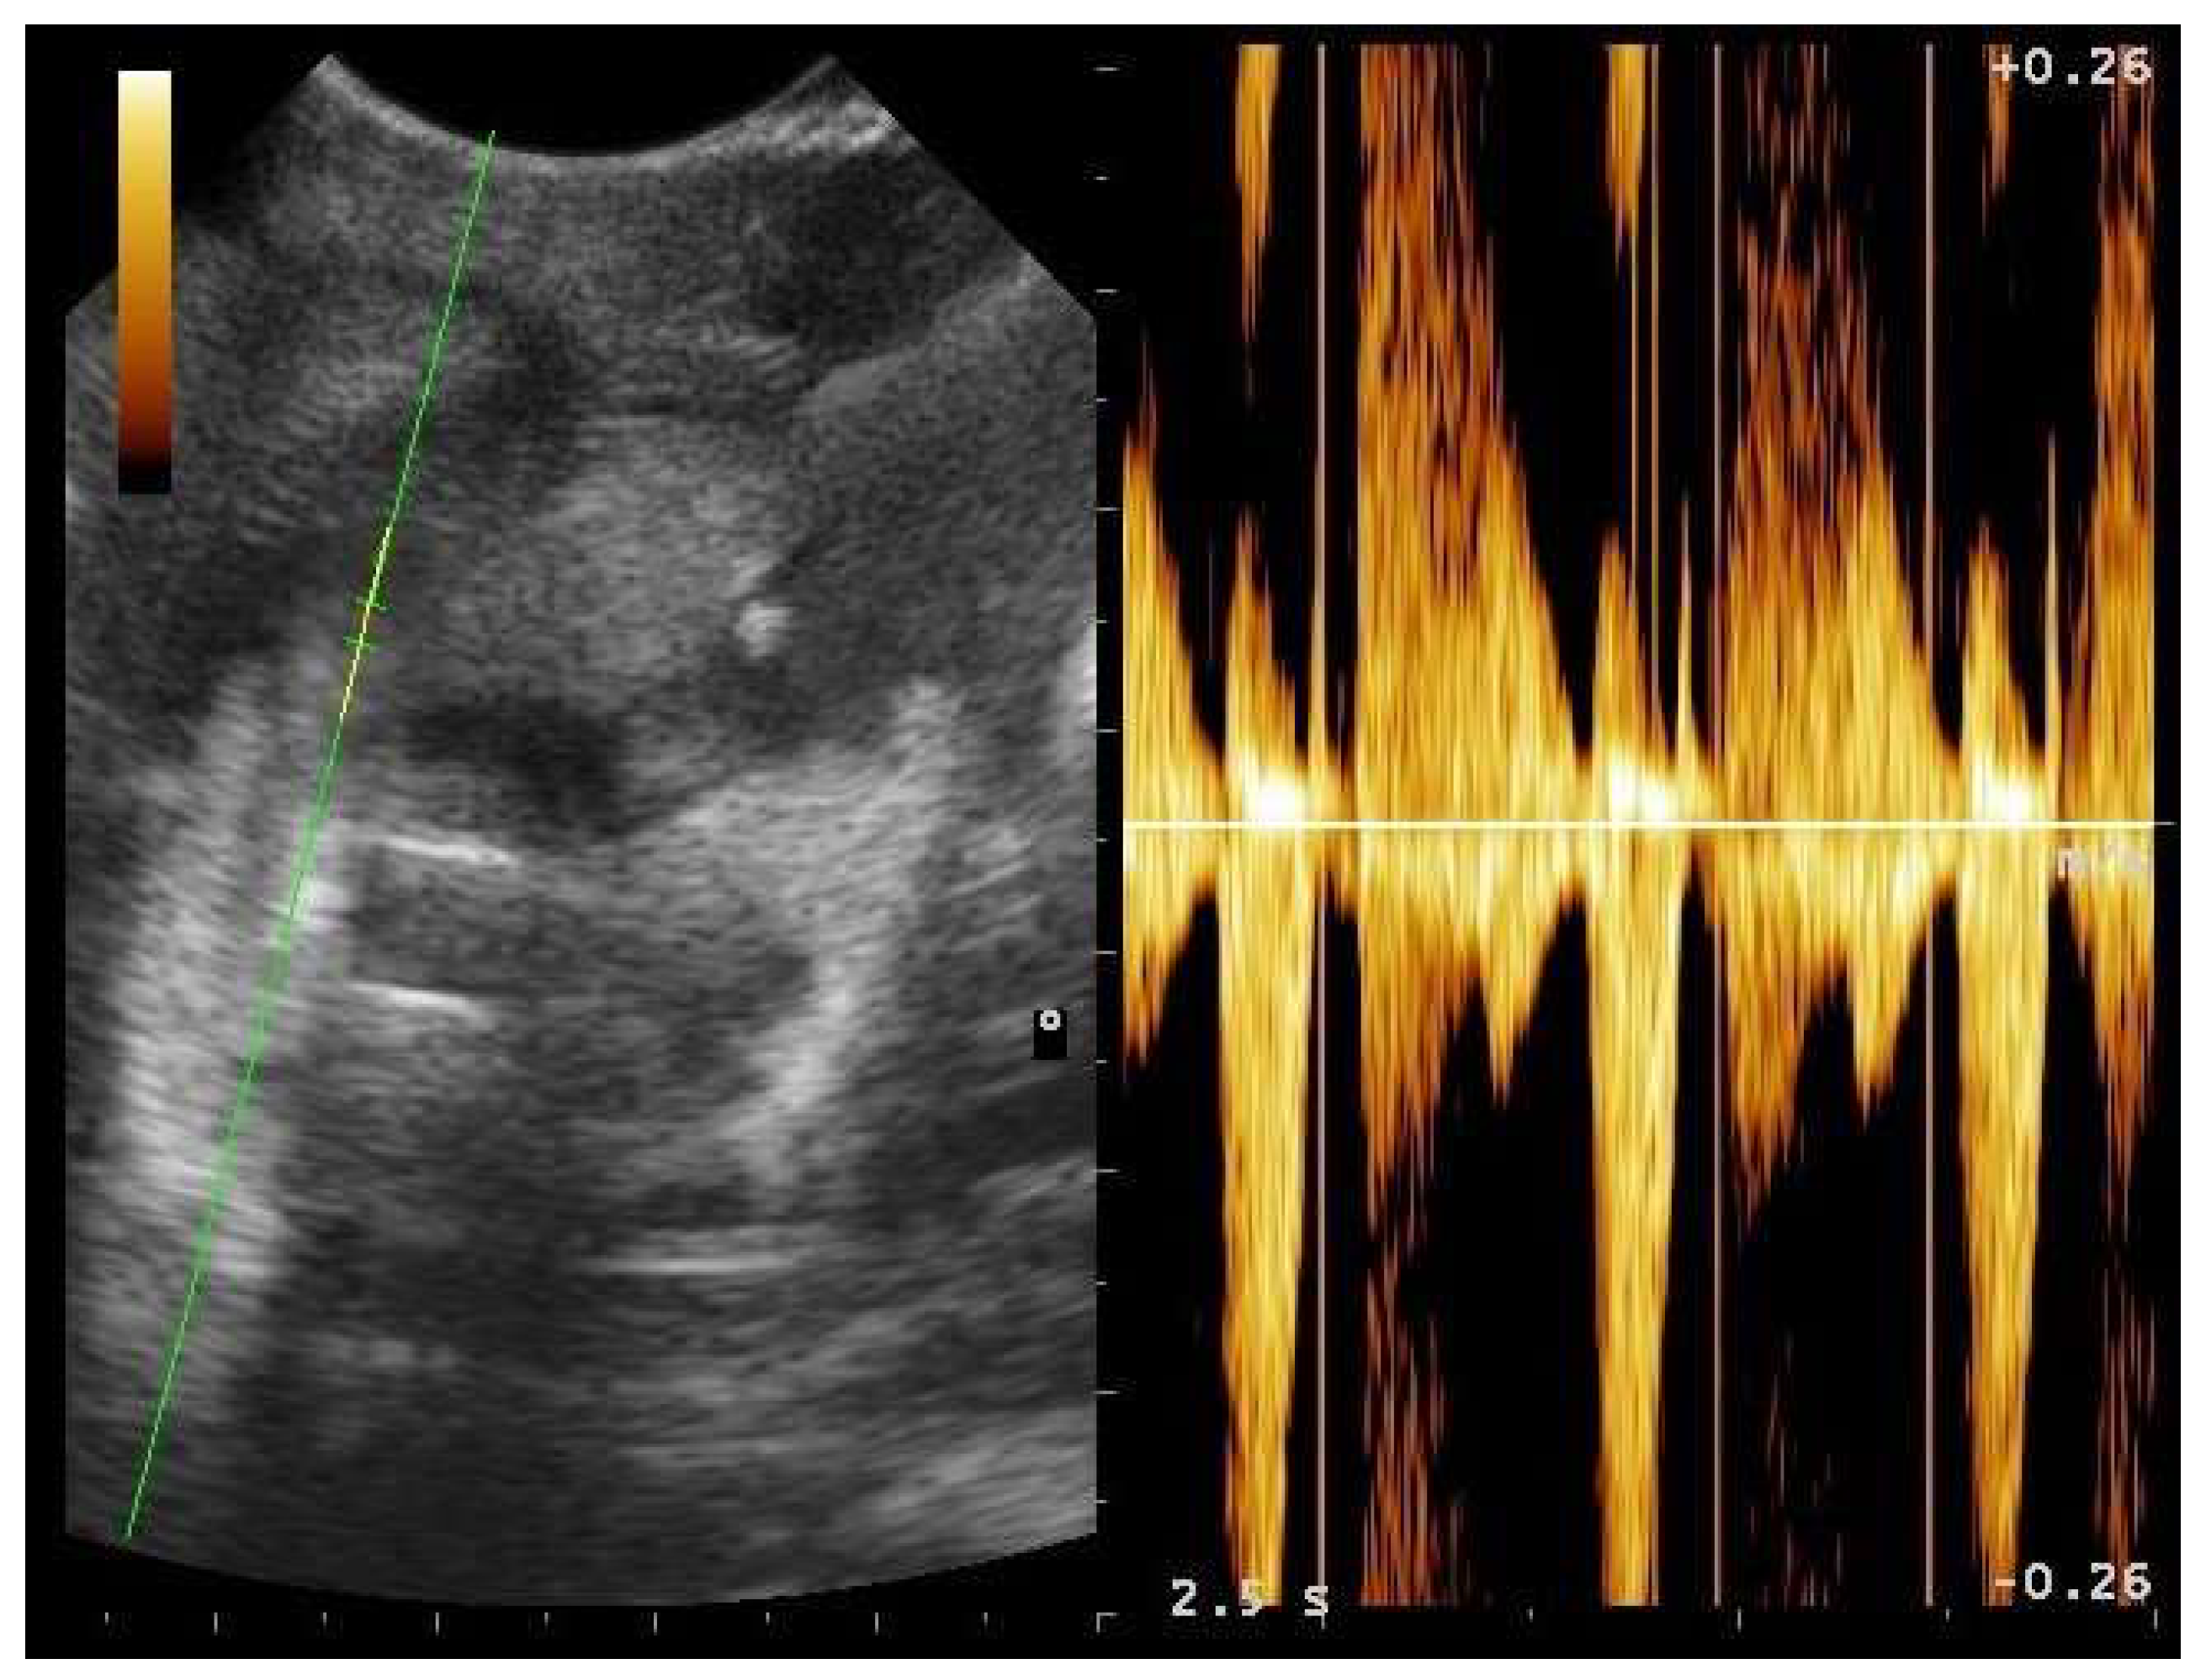

- Garcia, V.C.; Almeida-Santos, S.M. Reproductive cycles of neotropical boid snakes evaluated by ultrasound. Zoo Biol. 2021, 1–10. [Google Scholar] [CrossRef]

- Bigliardi, E.; Denti, L.; De Cesaris, V.; Bertocchi, M.; Di Ianni, F.; Parmigiani, E.; Bresciani, C.; Cantoni, A.M. Colour Doppler ultrasound imaging of blood flows variations in neoplastic and non-neoplastic testicular lesions in dogs. Reprod. Domest. Anim. 2019, 54, 63–71. [Google Scholar] [CrossRef]